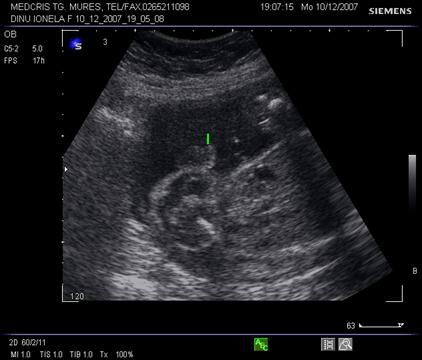

Fig. nr. 178. Planul 2 de sectiune a cordului cu aspectul inimii in 5 camere, emergenta aortei se adauga celor 4.